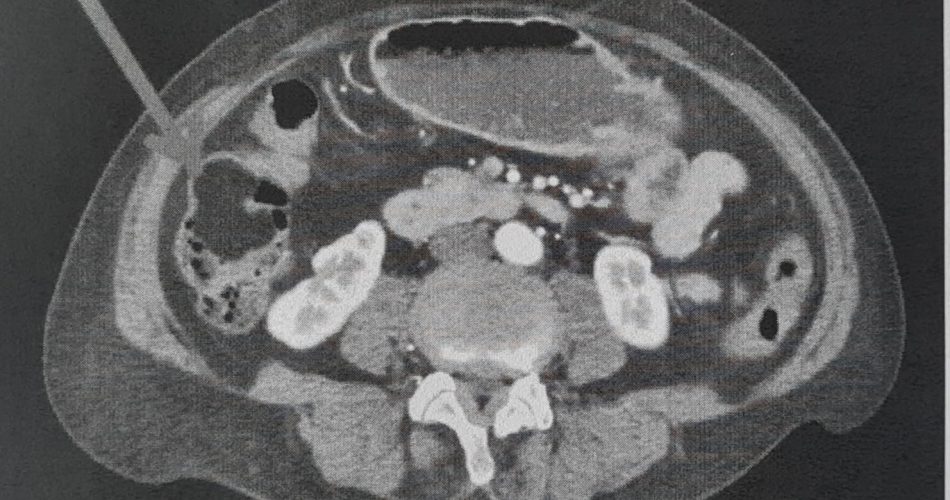

chirurgia corato - tc addome che evidenzia la massa tumorale

Gli approfondimenti diagnostici eseguiti, infatti, hanno chiarito un quadro clinico complesso e rivelato – grazie ad una Tac addome – una subocclusione intestinale dovuta alla presenza di una massa tumorale di oltre 6 cm di diametro, sviluppatasi all’interno della parete del colon destro, confermata da una successiva colonscopia. Dopo il completamento delle indagini strumentali e un’attenta valutazione anestesiologica, la paziente è stata sottoposta ad Emicolectomia destra laparoscopica, un intervento chirurgico mini-invasivo per la rimozione del tumore annidato nella parte destra del colon. Il decorso postoperatorio, con dimissione dopo dieci giorni, è stato seguito in stretta collaborazione con il team di cardiologi e internisti del presidio.